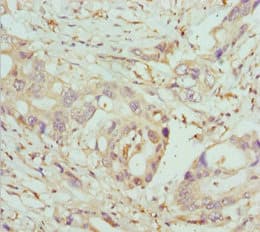

Rabbit Polyclonal COG5 antibody. Suitable for WB, IHC-P and reacts with Mouse, Human samples. Immunogen corresponding to Recombinant Fragment Protein within Human Conserved oligomeric Golgi complex subunit 5 aa 1-300.

Applications IHC-P, WB